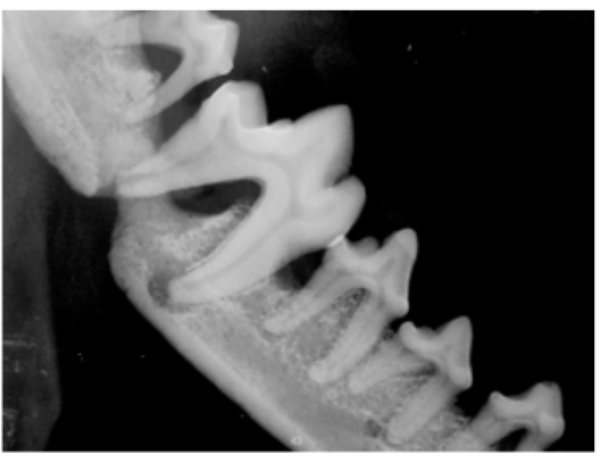

Without a dental X-ray, please be prepared for surprises. For example, with conditions like severe periodontal disease, the jaw is often not in good shape before a dental procedure. A frail jaw can easily fracture during surgery—not a good surprise!

Check out this pre-operative X-ray below, taken before any surgery was done. This X-ray shows the owner that teeth must be extracted and a splint applied.

Pre-existing pathology, like jaw integrity, needs to be documented. Pre-operative X-rays show the condition, and post-surgery X-rays prove a job well done.